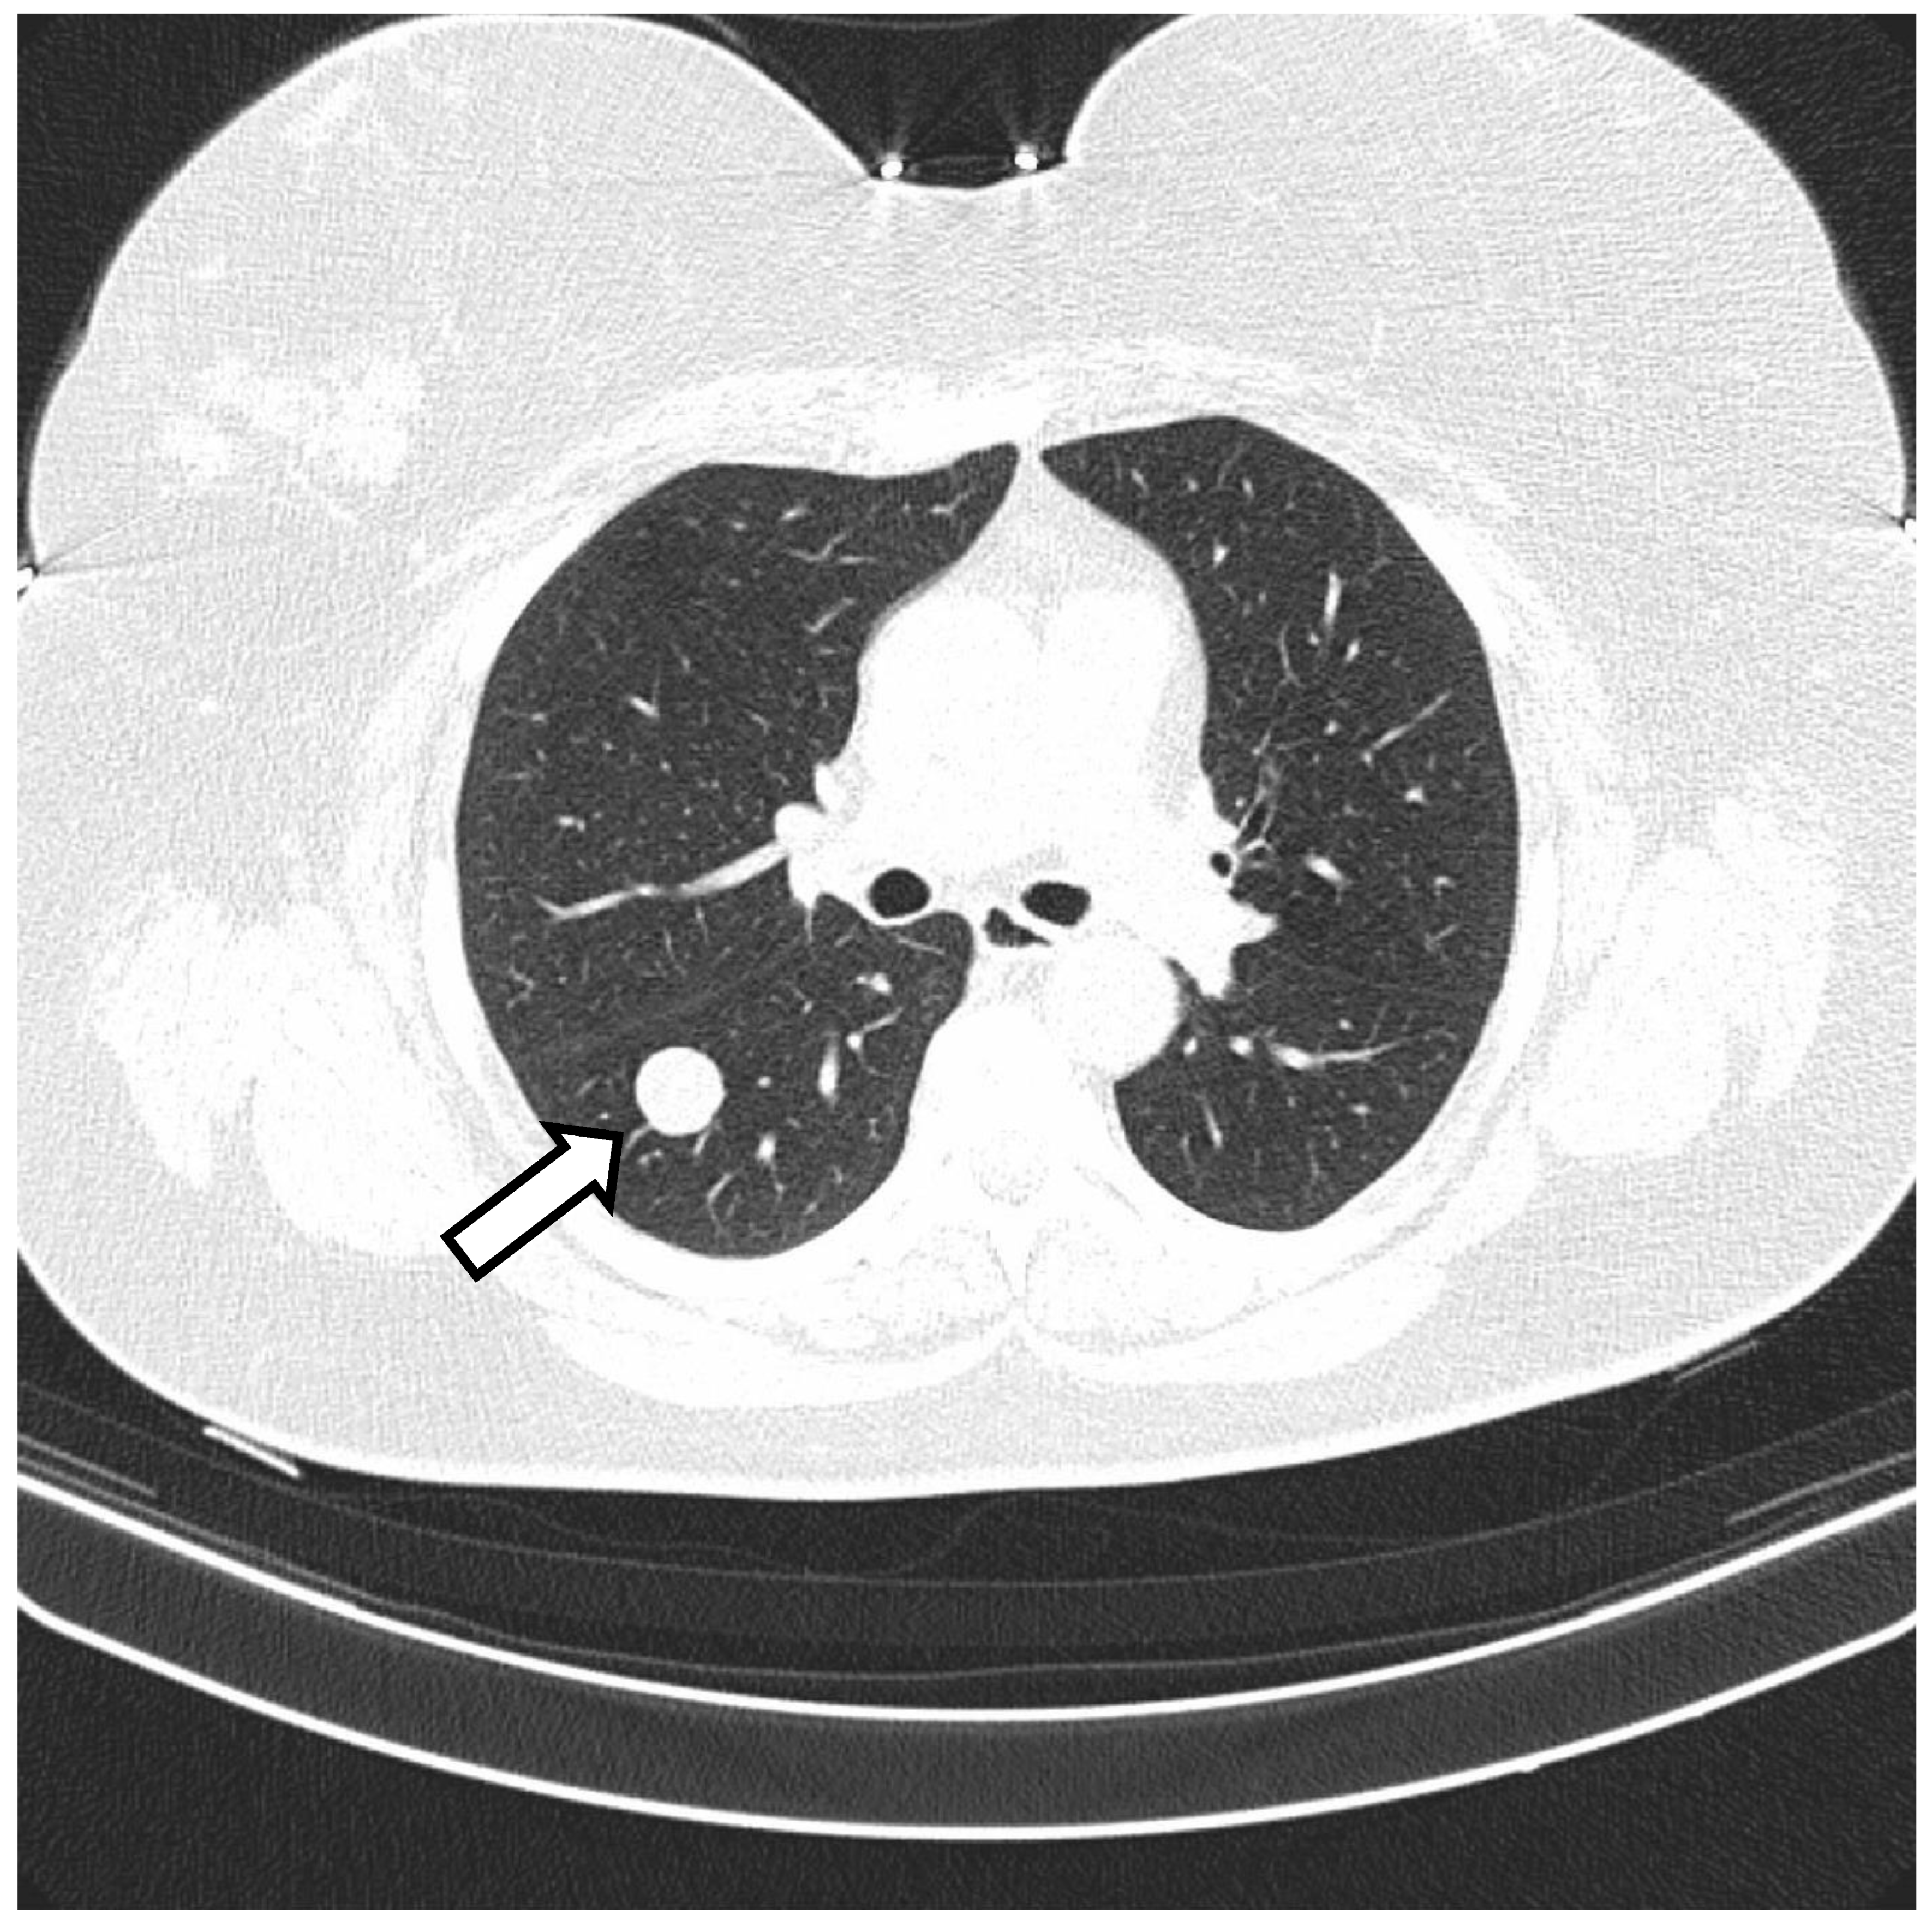

2. Case 1